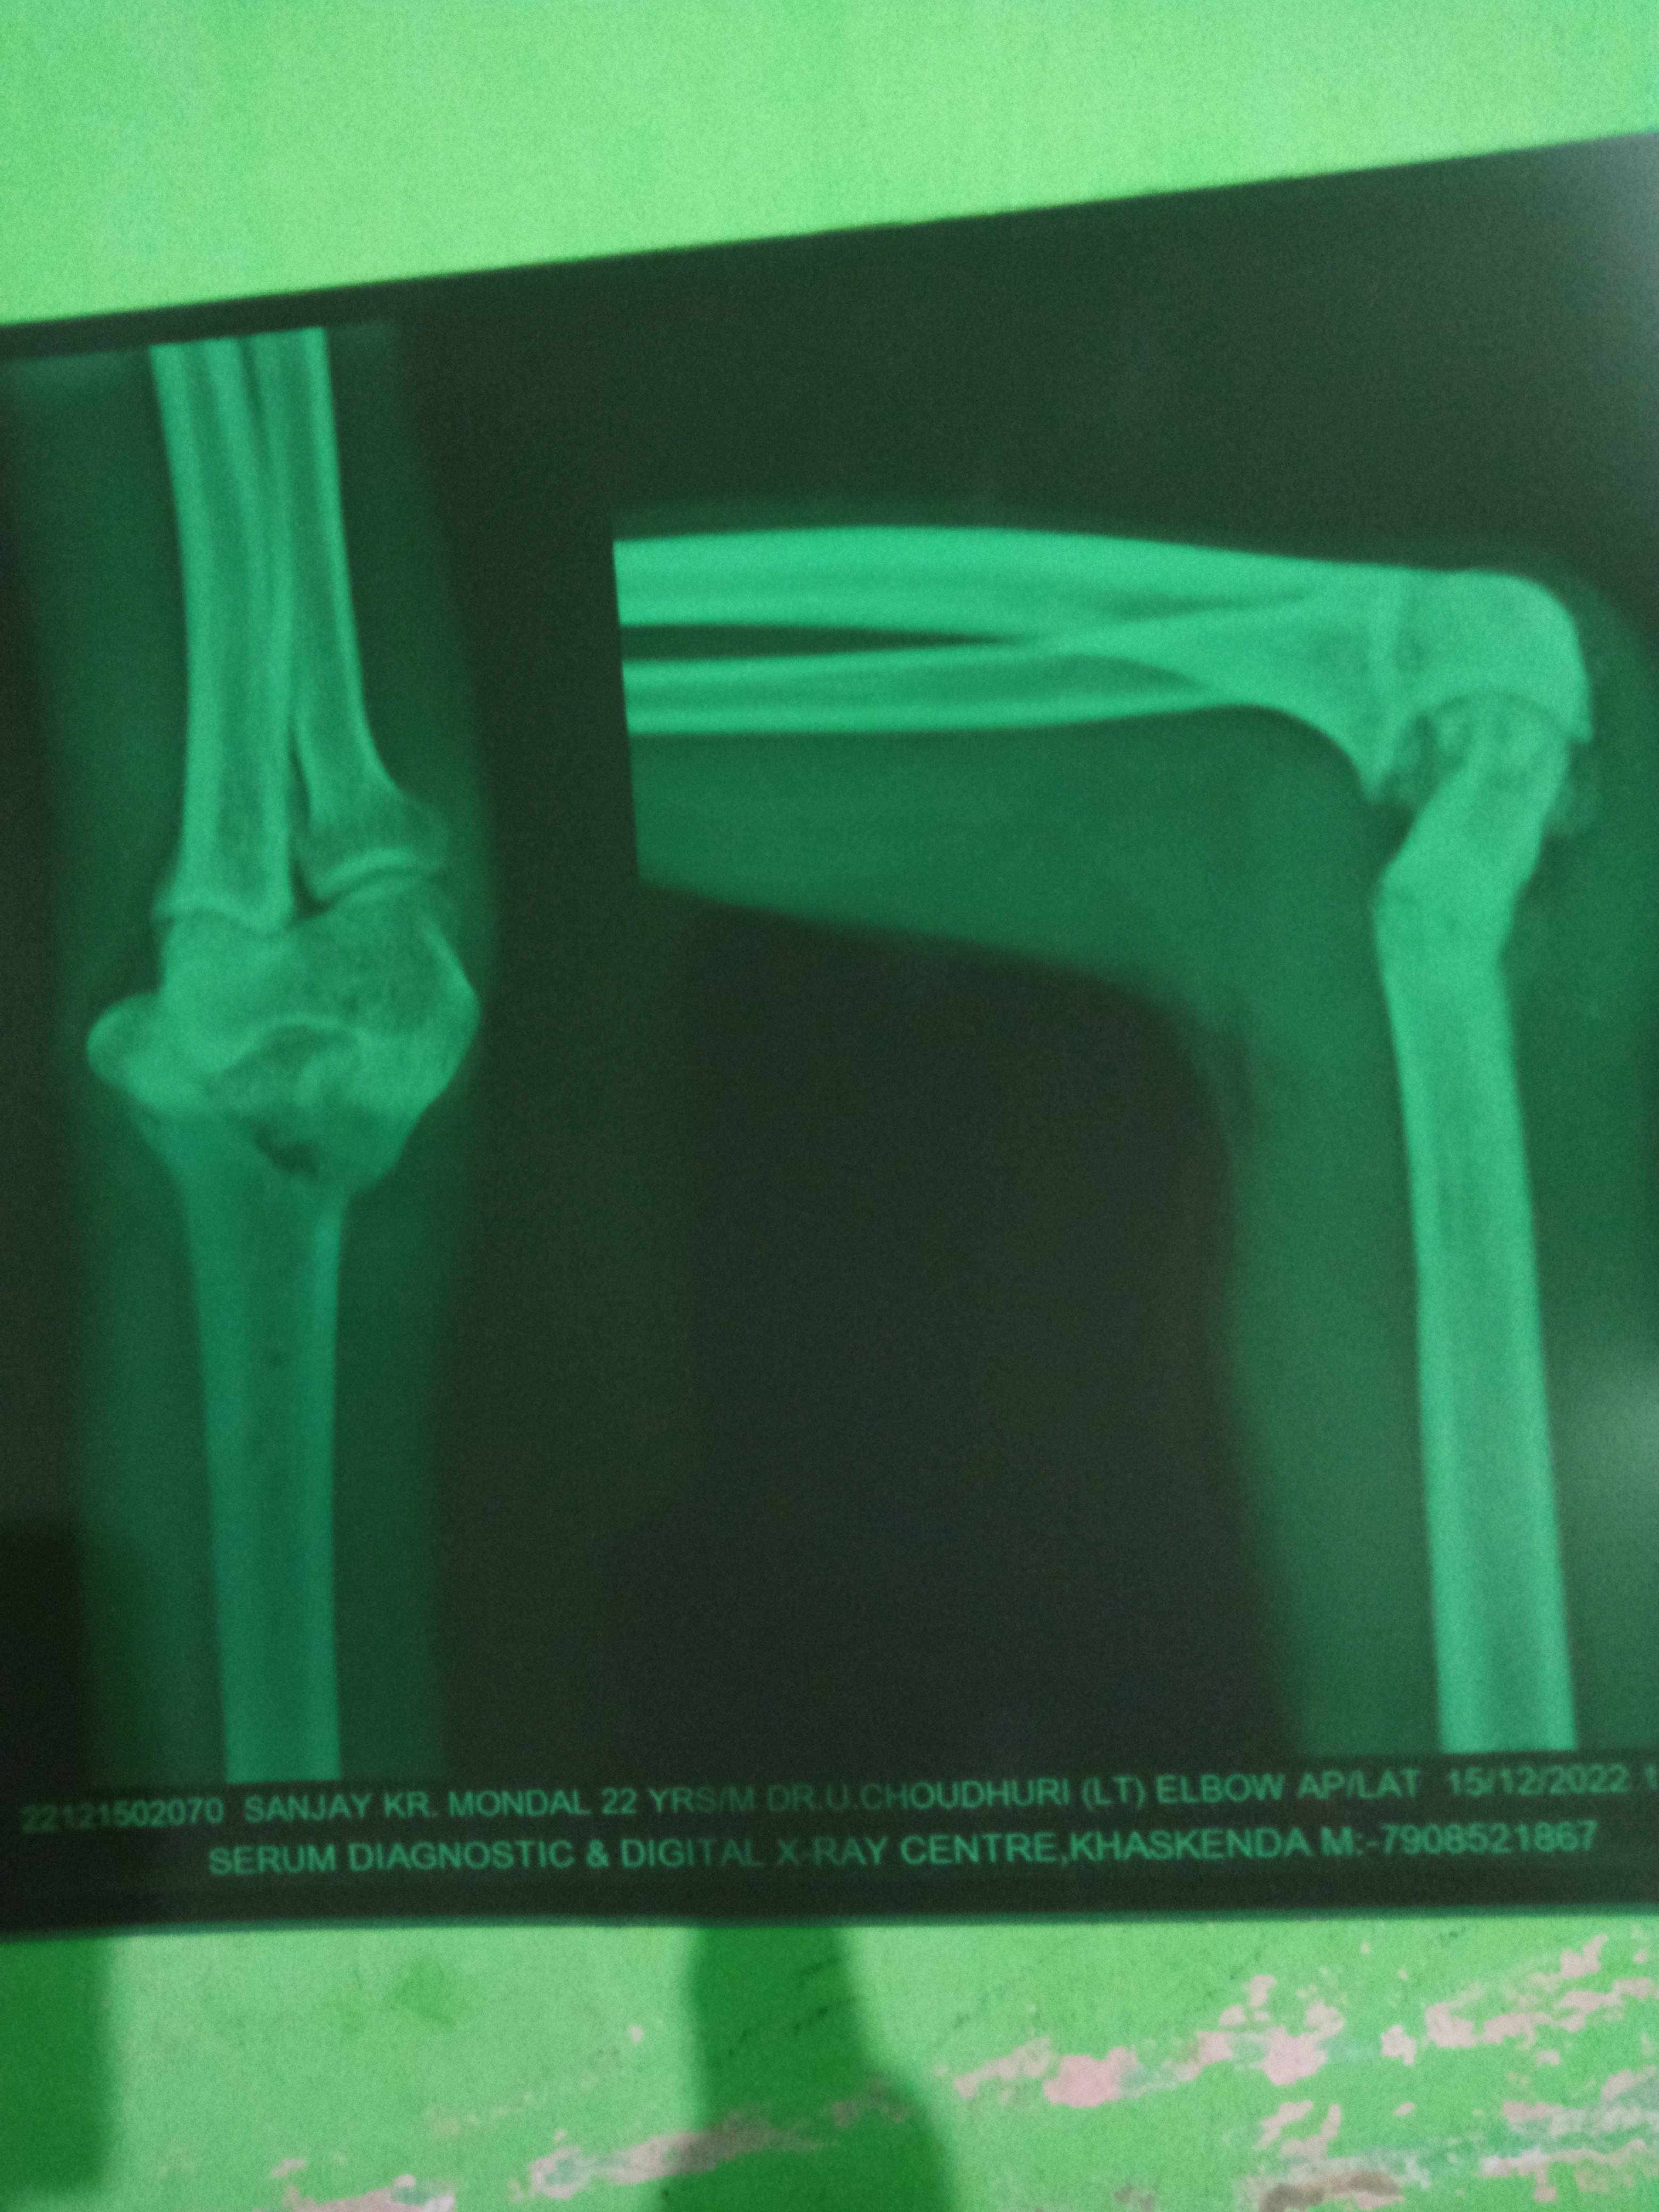

Sanjay Kumar Mondal

Oestotomy correction of right elbow ka 3month pahle hua tha pr Hand ka movement nahi ho paa raha hai physiotherapy bhi karwa rahe hai